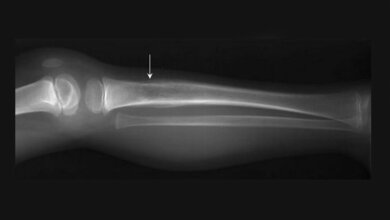

In den meisten Fällen besteht die Behandlung von metastasierten Tumoren in der systemischen Therapie der zugrundeliegenden Krebserkrankung. Es kommt aber vor, dass der Primärtumor gut unter Kontrolle gebracht werden konnte, nicht aber einzelne Metastasen. Gerade Knochenmetastasen gehen oft mit Schmerzen einher, die die Lebensqualität der Patientinnen und Patienten stark beeinträchtigen können. Die Metastasen zerstören den Knochen in den befallenen Bereichen, sodass die Stabilität abnimmt und es zu Knochenbrüchen kommen kann. Besonders gefährlich sind Wirbelkörpermetastasen, da Frakturen entsprechend zu Lähmungen führen können.

Bei Knochenmetastasen stellt die Strahlentherapie eine hocheffektive Therapie zur lokalen Schmerzkontrolle und Wachstumshemmung der Metastasen dar, so die DEGRO. Die moderne Radiotherapie biete hier verschiedene hocheffektive Behandlungsoptionen. In den meisten Fällen werde diese als eine fraktionierte konventionelle Radiotherapie (cRT) über 3-4 Wochen verabreicht, sodass jeden Tag eine einzelne „Bestrahlungssitzung“ erfolge. Um hier möglichst schonend, aber langfristig effektiv zu sein, könne sich das bis zum Erreichen der notwendigen Gesamtdosis über mehrere Wochen erstrecken. Die Fraktionierung sei notwendig, um Nebenwirkungen zu minimieren bzw. dem gesunden Gewebe in der Tumorumgebung Zeit zur Erholung zu geben. Moderne Techniken der Präzisionsbestrahlung ermöglichen heute, in wenigen Sitzungen auch höhere Strahlendosen zu applizieren (Hypofraktionierung), ohne umliegende Strukturen zu belasten. Durch eine noch präzisere Positionierungstechnik können in manchen Fällen mit der stereotaktischen Körperbestrahlung („Stereotacic Body Radiotherapy“/SBRT) noch höhere Einzeldosen verwendet werden, sodass sich die Zeitdauer von mehreren Wochen auf wenige Tage verkürze. Entscheidend sei bei der Stereotaxie aber die präzise Definition bzw. Festlegung des Zielvolumens und die genaue Positionierung der Strahlen. Die Bestrahlungsplanung erfolge daher mittels Bildgebung (CT, MRT) in 3D-Technik und die Bestrahlung selbst erfolge ebenfalls bildgebungsgeführt. Es komme aber nicht jede Metastase für eine stereotaktische Bestrahlung in Frage, da dies von der Größe und auch der Nähe zu kritischen Strukturen abhänge, betont die DEGRO.

Die VERTICAL-Studie, eine Phase-II-Studie [1], verglich in einer präspezifizierten Sekundäranalyse der PRESENT-Studie [2] die konventionelle Strahlentherapie mit der stereotaktischen Körperbestrahlung zur Behandlung schmerzhafter Knochenmetastasen. Insgesamt wurden 110 Patientinnen und Patienten zu gleichen Teilen randomisiert in zwei Gruppen entweder mit cRT (1x8 Gy, 5x4 Gy oder 10x3 Gy) oder SBRT (1x18 Gy, 3x10 Gy oder 5x7 Gy) behandelt. Einschlusskriterien waren beispielsweise ≤2 schmerzhafte Knochenmetastasen, ein Karnofsky-Index (Score von 0-100, der die Alltagsbeeinträchtigung von Krebspatientinnen/-patienten misst, z.B. Aktivität und Selbstversorgung) von ≥50 Punkten, ein Schmerzscore von ≥3 Punkten (von 0-10) und eine zu erwartende Überlebensdauer von ≥3 Monaten. Erfasst wurden über den Verlauf von drei Monaten Veränderungen der allgemeinen Lebensqualität (QoL), physische Funktionen und emotionales Befinden sowie funktionelle Störungen und psychosoziale Aspekte anhand QLQ-Fragebögen („European Organization for Research and Treatment of Cancer QoL Questionnaire Core 15 Palliative Care and QLQ Bone Metastases 22 modules“).